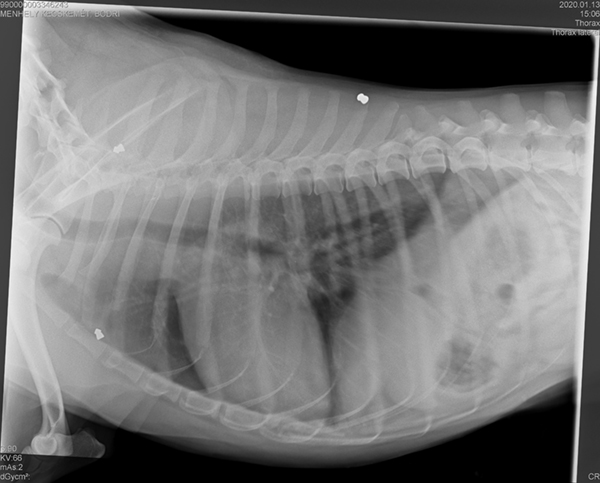

Zu allem Unglück fand man bei einem Röntgen heraus, dass wohl mal auf Bodri geschossen wurde. In seinem Körper befinden sich 3 Kugeln, die nun nicht mehr entfernt werden können.